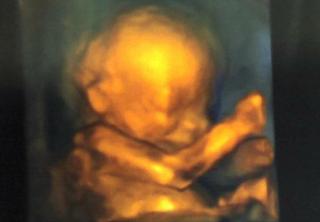

@majoslava juuuj no to je foto 🙂 prosim ta kolko dopredu sa treba objednat? A kolko Ta to vyslo?

@veronika1417 mna objednával môj Dr. lebo som mala zlé výsledky triple testu... cez Dr. som za vyšetrenie platila 39eur ... jedna fotka 10eur... video bolo tuším 64eur...

@veronika1417 ja som nemala na výber... bud odber plodovej vody alebo zaplatiť vyšetrenie.... a ked som tam už bola tak som si jednu fotku na pamiatku zobrala 🙂